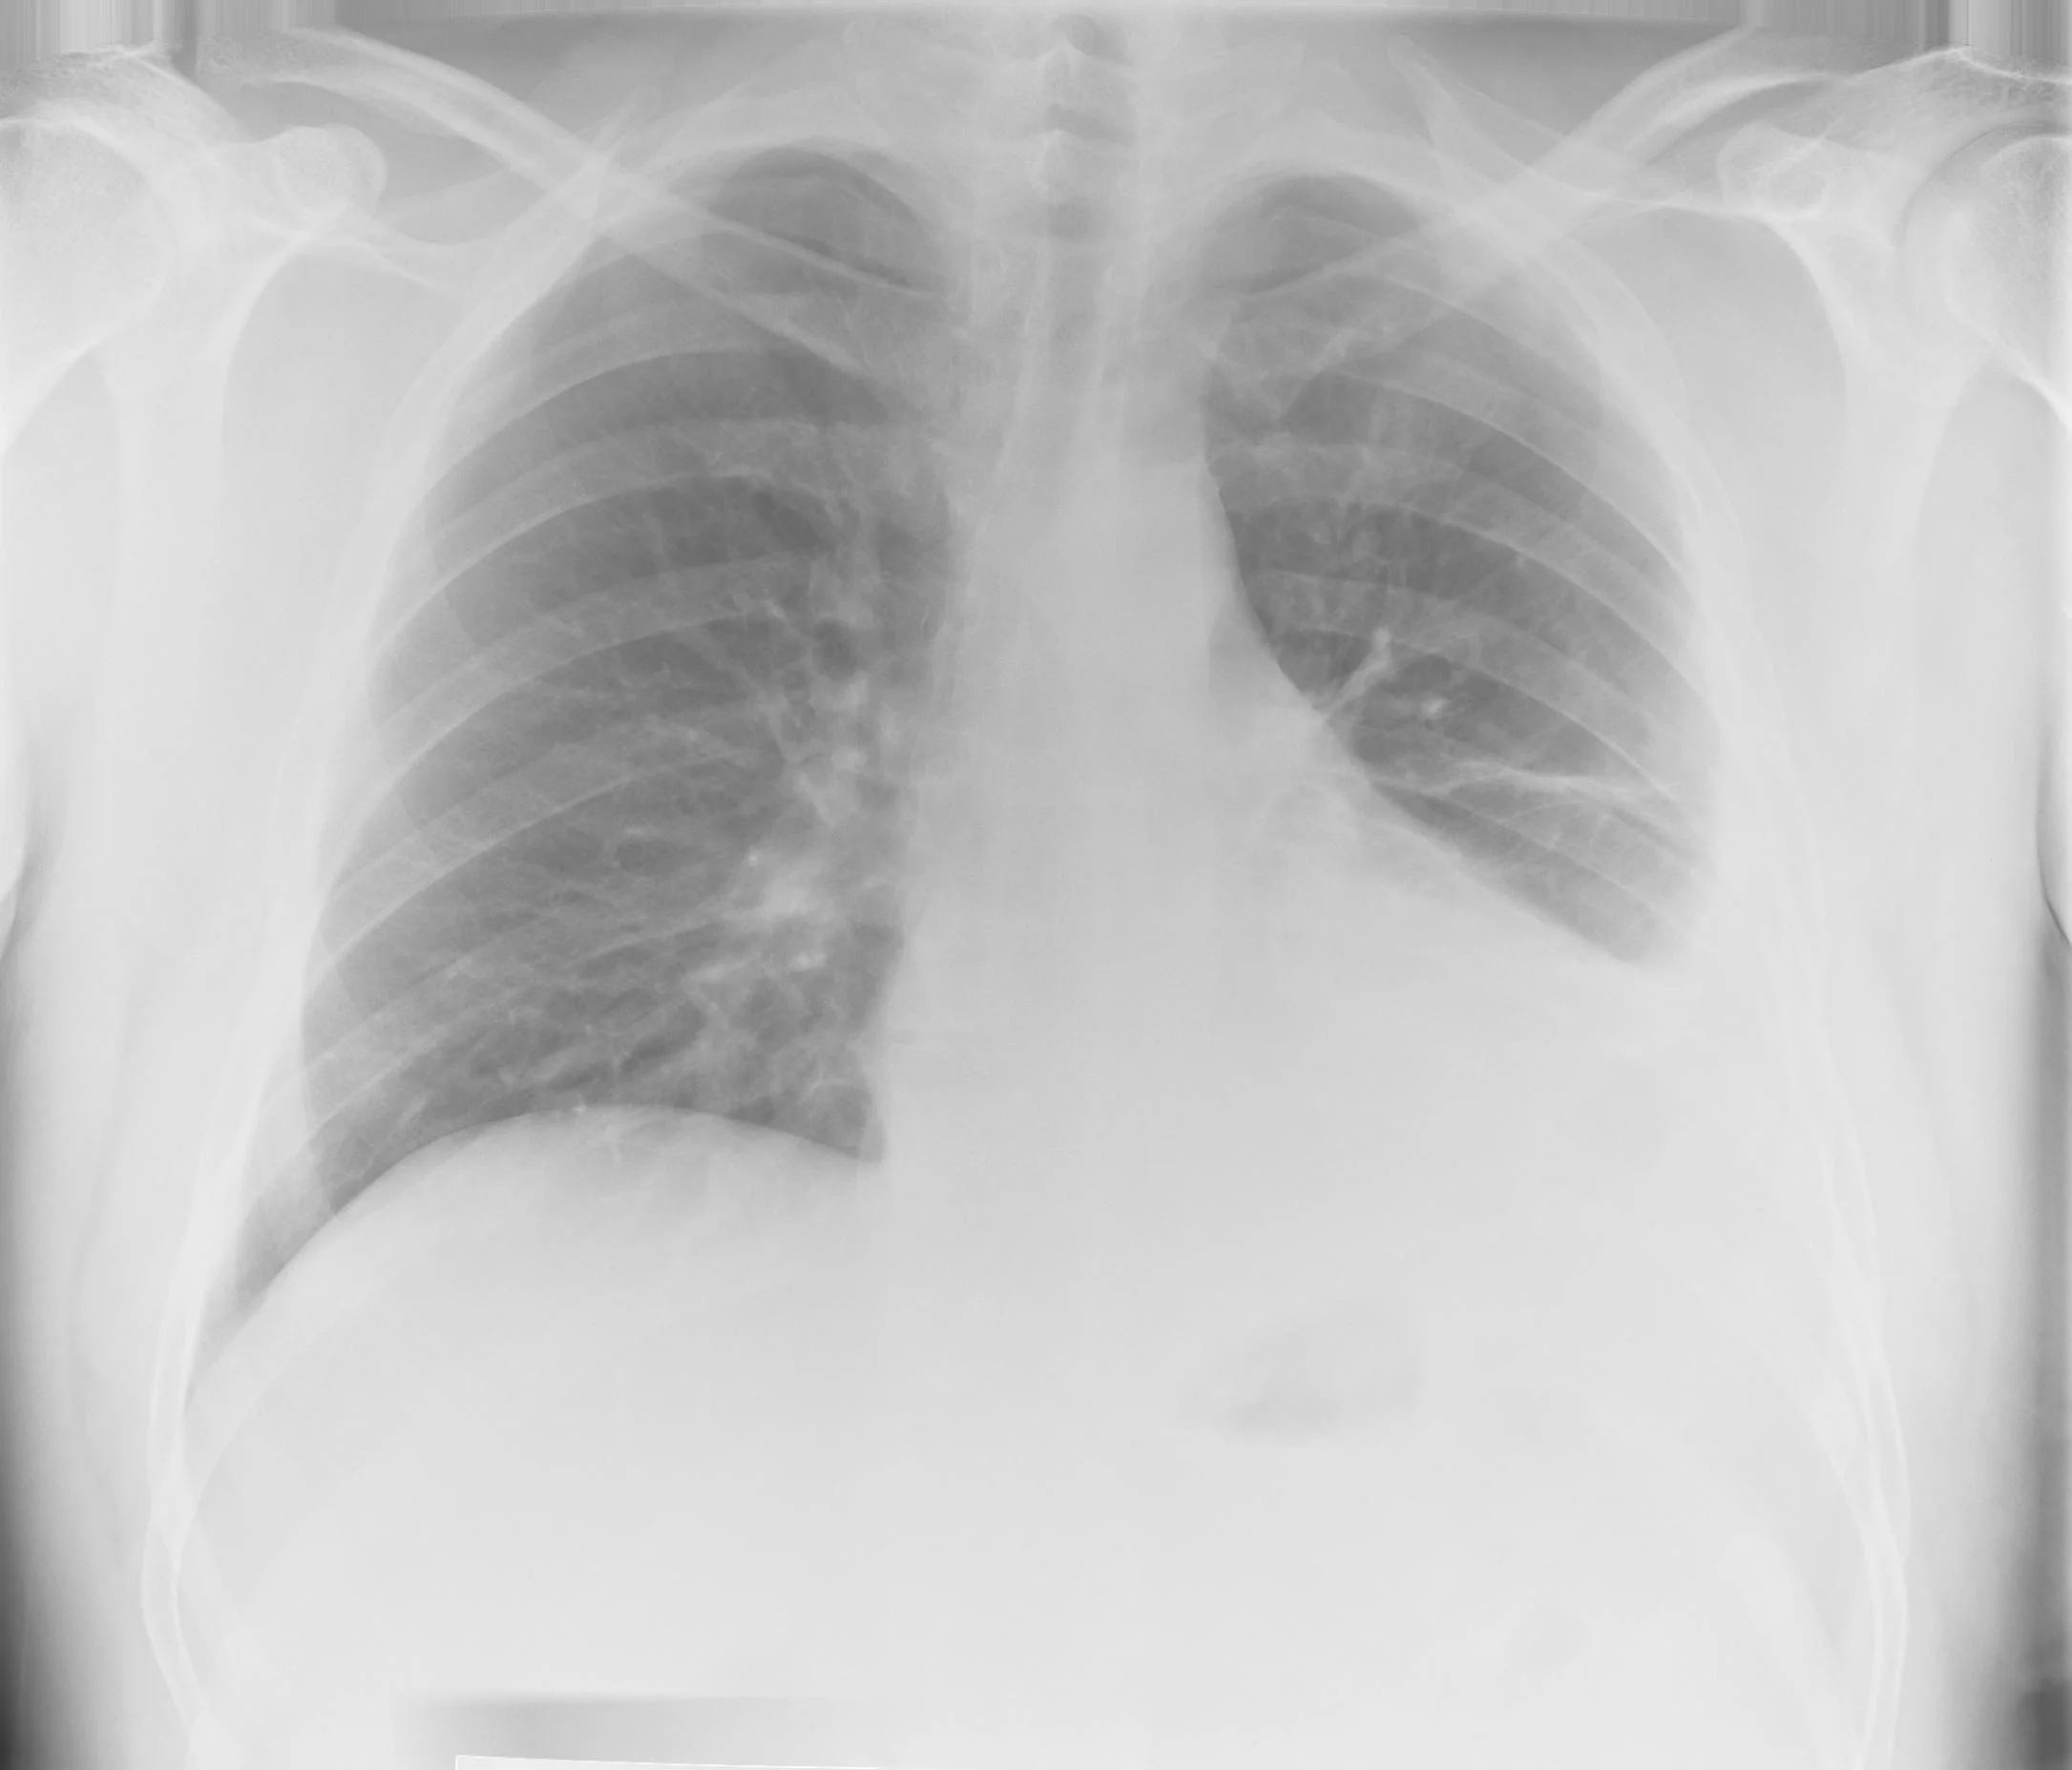

Lung Air Fluid Level Fluid Level Meaning In Medical what is fluid balance? It's when you have too much fluid in your body. fluid overload is also called hypervolemia. A systematic approach to axr interpretation is essential to avoid missing significant pathological. identify potential risk factors and contraindications related to fluid management in patients. this article discusses the general concepts of the formation of fluid. Fluid Level Meaning In Medical.